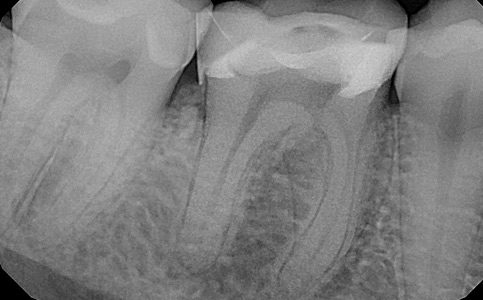

Po dokładnej diagnostyce ząb zakwalifikowano do leczenia endodontycznego. Leczenie przeprowadzane zostało przez naszego specjalistę pod mikroskopem.

Zobacz efekty przeciągając suwak w prawo lub w lewo.